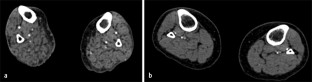

Abb. 2

Neue Verfahren wie die hochauflösende periphere quantitative Computertomographie (HR-pQCT) bieten die Möglichkeit, die Mikroarchitektur des peripheren Skeletts ohne Biopsie zu untersuchen. Mit der MR-Spektroskopie können zusätzliche Informationen über die Zusammensetzung des diabetischen Knochenmarks gewonnen werden: Beide Techniken helfen bei der Differenzierung von Diabetikern mit und ohne prävalente Frakturen und stellen daher eine Verbesserung gegenüber den derzeit gültigen Standardverfahren dar, befinden sich allerdings noch im Versuchsstadium.

Novel research imaging techniques, such as high-resolution peripheral quantitative computed tomography (HR-pQCT) provide non-invasive insights into bone microarchitecture of the peripheral skeleton. Using MR spectroscopy, bone marrow composition can be studied. Both methods have been shown to be capable of discriminating between type 2 diabetic patients with and without prevalent fragility fractures and thus bear the potential of improving the current standard of care. Currently both methods remain limited to clinical research applications.